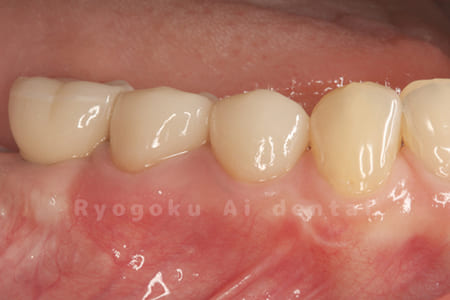

Case11

- 治療内容

- セラミッククラウン、セラミックインレー

-

- 治療費用

- 123,000円×2(セラミッククラン)、77,000円(セラミックインレー)

銀歯が取れて、ご来院された患者様です。奥歯2本をセラミッククラウン、手前の小臼歯をセラミックインレーで治療を行いました。

<リスク・副作用>

過度の咬合や衝撃で割れることがあります。